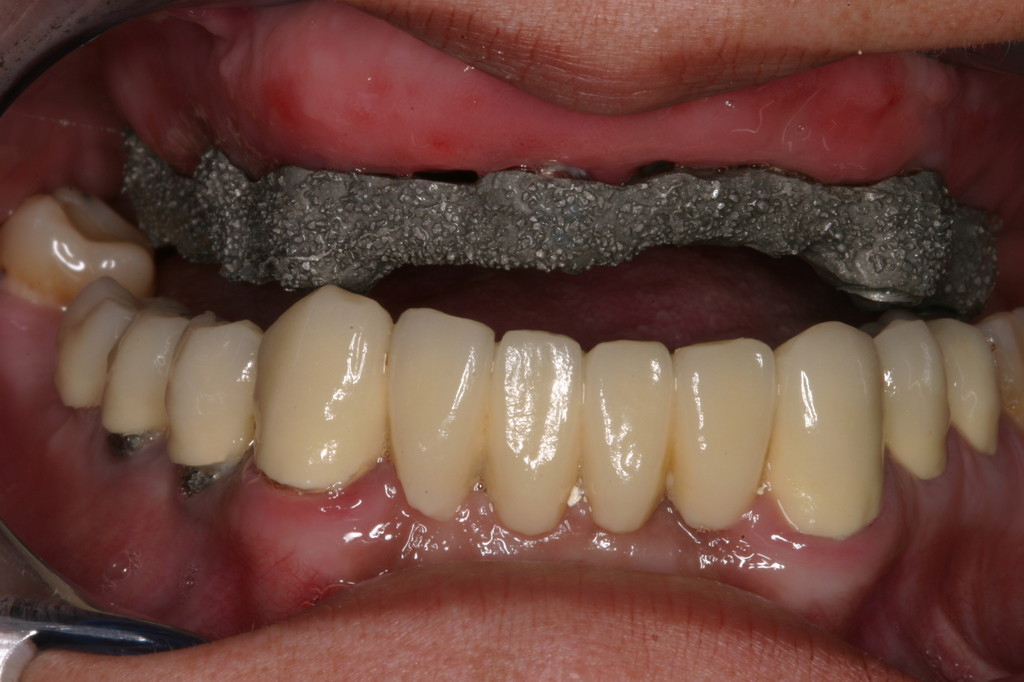

REHABILITACIÓN CON IMPLANTES Y CIRUGÍA PLASTICA PERIODONTAL.

REHABILITACIÓN CON IMPLANTES SIN CIRUGÍA.

REHABILITACIÓN CON IMPLANTES ,ENFERMEDAD PERIODONTAL AVANZADA.

REHABILITACIÓN IMPLANTOSORTADA EN MANDÍBULA Y MAXILAR.

REHABILITACIÓN ESTÉTICA CON IMPLANTES.